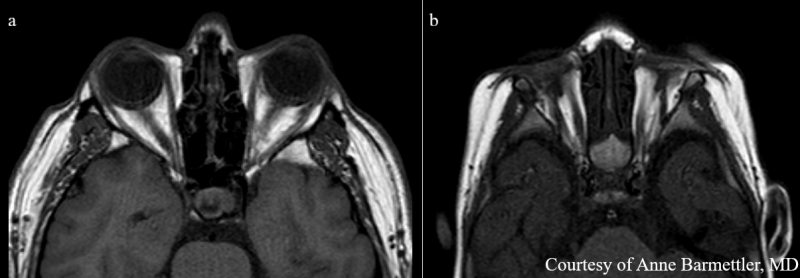

If an ocular malformation is suspected, an ultrasound should be performed to assess for the presence of optic structures [15]. Electrodiagnostics, such as flash visual evoked potentials, can be used to determine if there is residual functioning retinal tissue [15]. CT and MR imaging can further characterize contents of the globe, the degree of involvement of central optic nervous tissue, and to screen for co-existing CNS abnormalities [2]. Figure 2 compares an MRI of a patient with normal optic structures within the socket and a patient with anophthalmia. CNS abnormalities that may occur in syndromic anophthalmia include pituitary hypoplasia, hippocampal malformation, hypothalamic abnormalities, and fusiform gyrus defects [2][16]. Renal ultrasound is also recommended in patients with anophthalmia due to the high co-occurrence of ocular and renal pathology [15].

Figure 2: Axial T1 MRI of a patient with normal optic structures (2a) compared to MRI of a patient with anophthalmia (2b). Note the complete absence of globes and aplasia of optic nerves as compared to the normal image. Extraocular muscles can still be seen within the socket. Image courtesy of Anne Barmettler, MD.